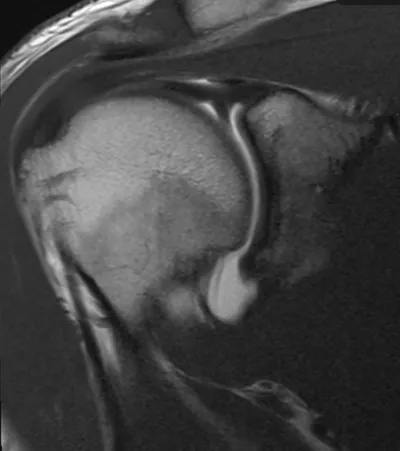

9 imagesPosterior glenoid labral tear

Arthrogram

4/11/2026